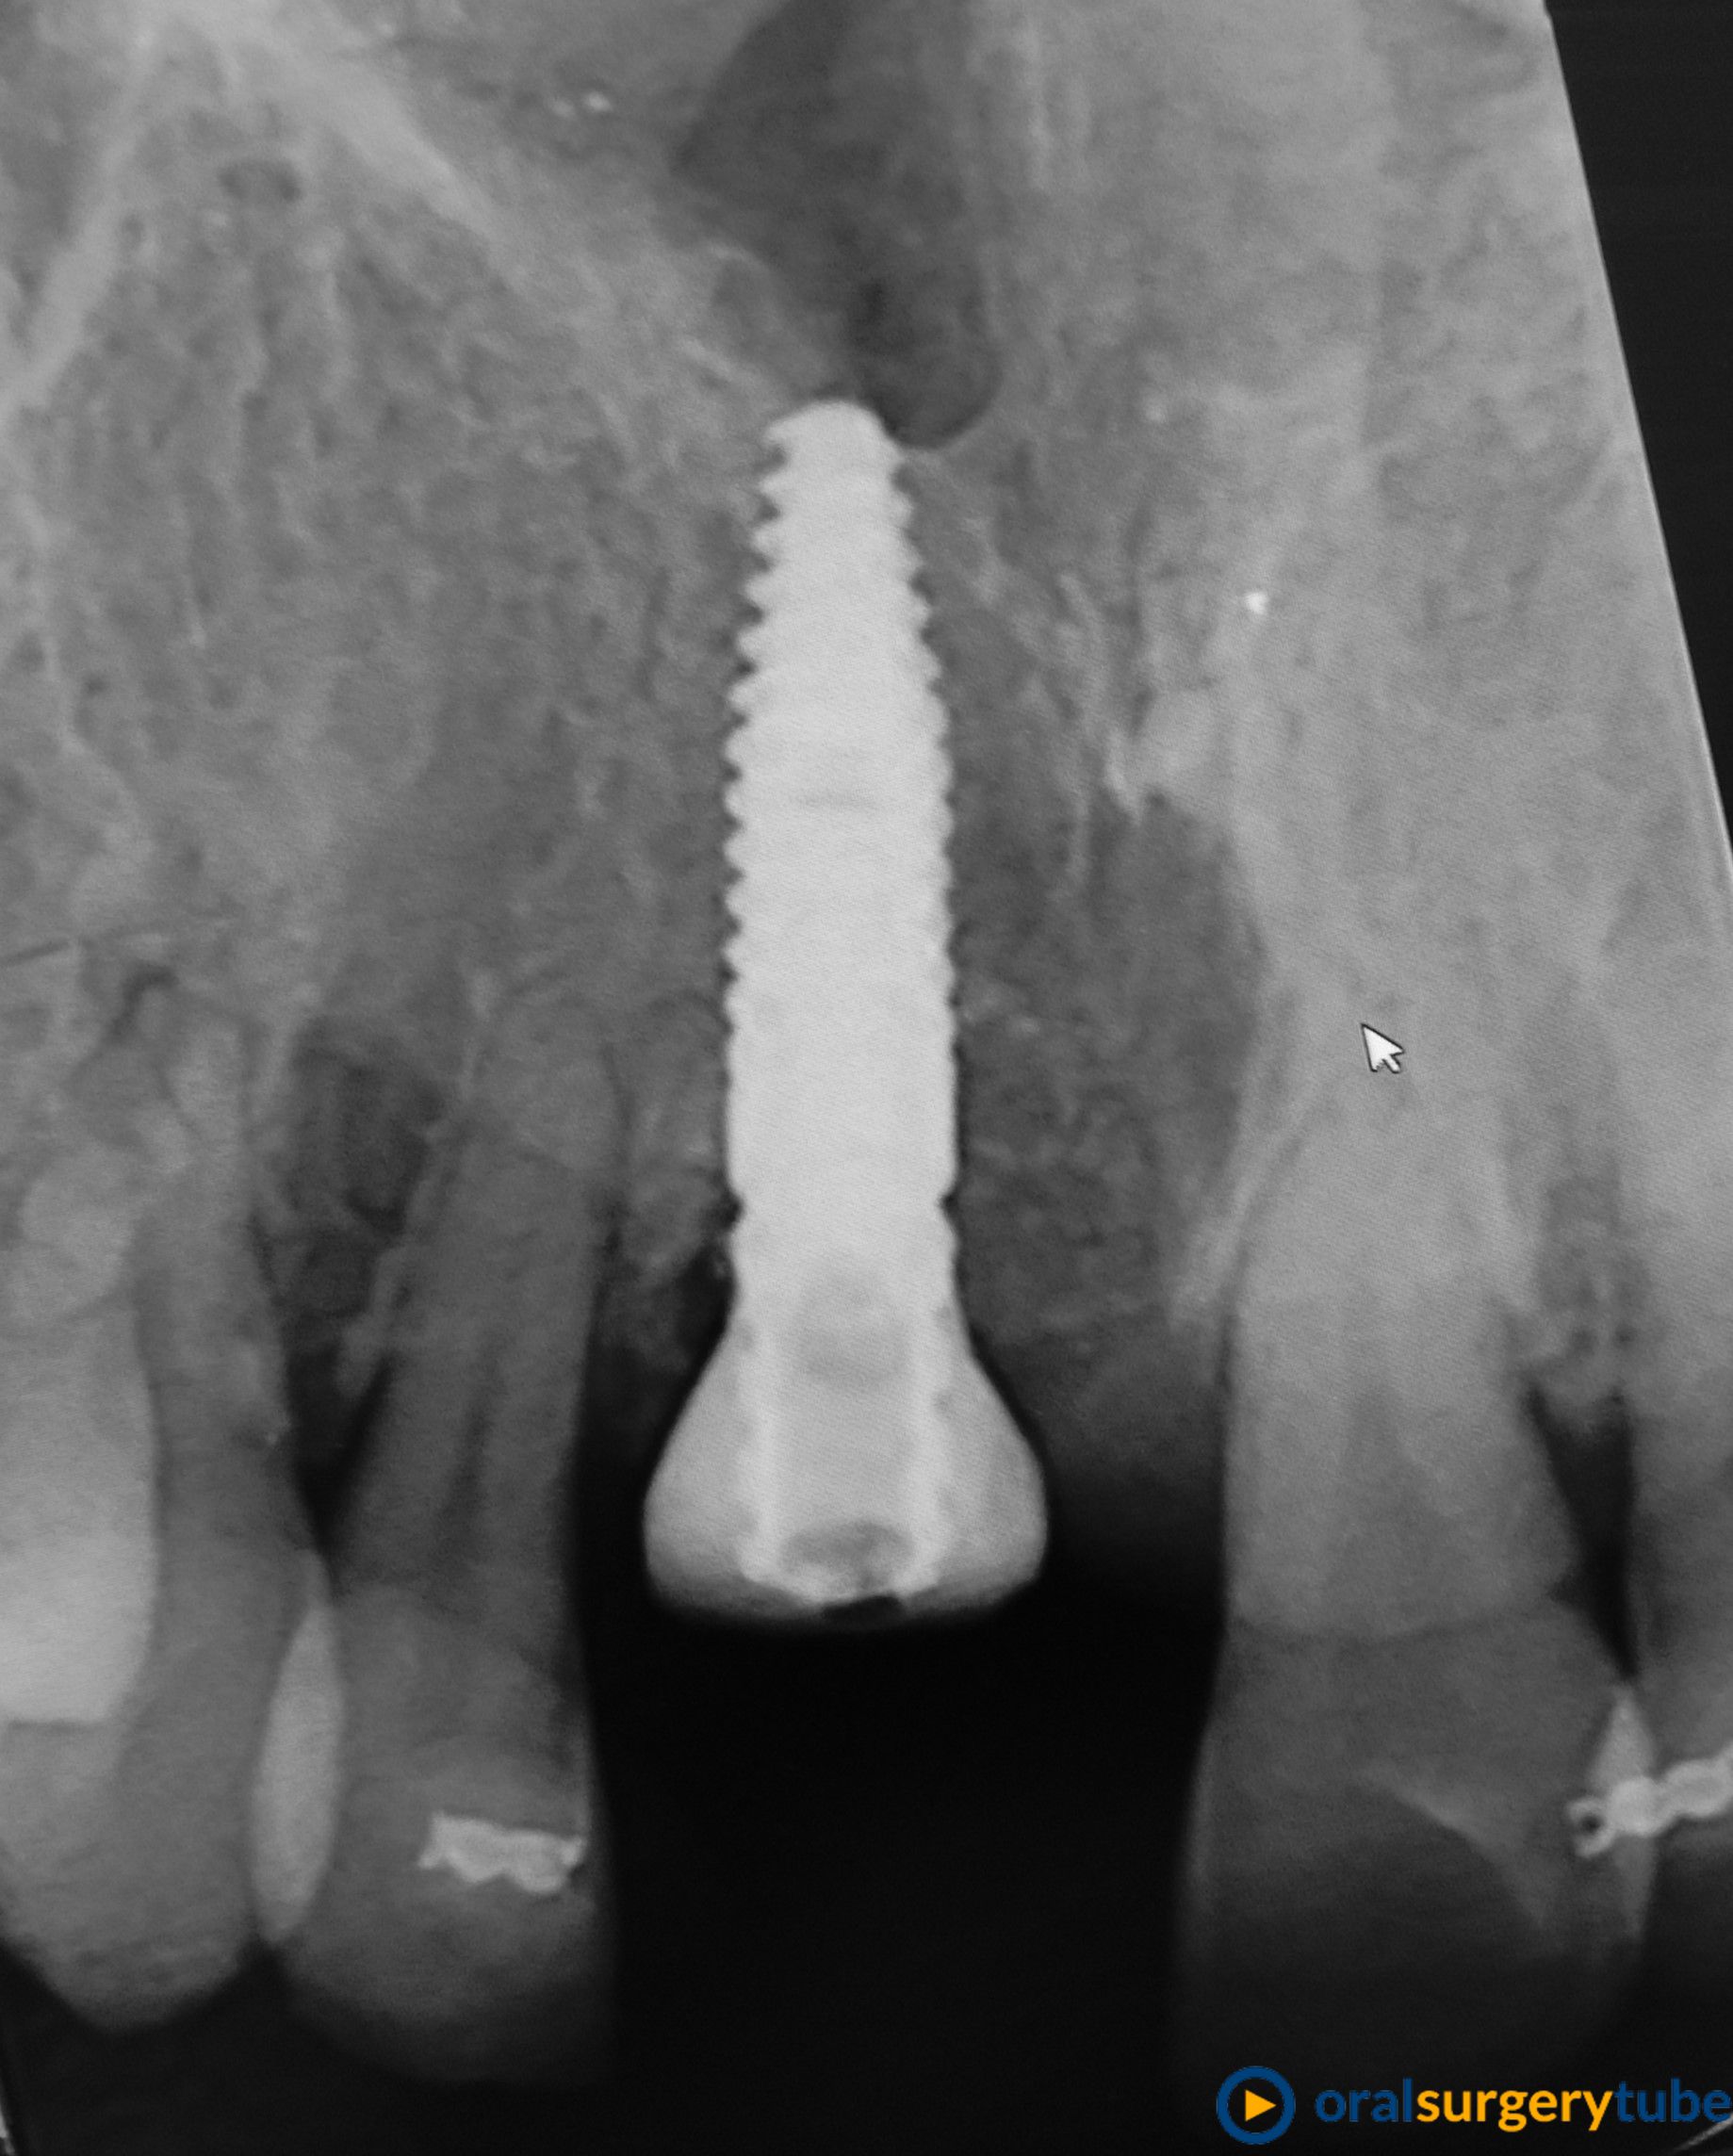

Paciente mujer joven, fumadora y de higiene regular. Con periodontitis moderada estabilizada pero con mal mantenimiento y con un proceso muy avanzado en el 21. Se le realiza en el mismo acto la extracción, legrado y lavado profuso, fresado y colocación guiada del implante con torque de 20N . Y después se regenera el aveolo con mix de autólogo de rama rascado con un micross y Bioss collagen y un injerto de tuberosidad en vestibular. No se hace carga inmediata por la baja estabilidad, se coloca y tapón de cicatrización y periacryl para sellar. Buscando un tratamiento similar (salvando mis infinitas limitaciones y distancias) a los protocolos de actuación de dos gigantes como Mesquita (implanteperio) y/o el de David González y su articulo de 3 Layers para alveolos sin tabla. Me decido por esta opción ya que todo lo que fuese levantar un colgajo sería al 100% un desastre estético y no estoy capacitado para un bloque mixto de tuberosidad ósea y blanda. Quizá haya fallado mi diagnostico o mi técnica.

Aparentemente la cicatrización es buena, asintomático y con buen aspecto. Pero en el control a 4 meses veo muchísima reabsorción de mi regeneración en vestíbulo. Sería por el potencial osteoclástico en ese lecho? o por no poner una capa de reabsorción lenta en la parte más externa?... en unos días probaré a ver si no me quedo con el implante en la mano.